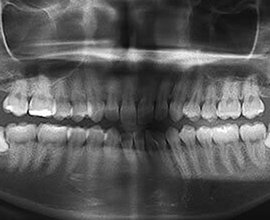

• 術前 画像

術前

下顎の左右に親知らずがあります。清掃が非常に困難で、隣の歯を虫歯にしてしまうリスクが高いため抜歯しました。2本とも傾いて生えているので、水平埋伏智歯の抜歯となりました。